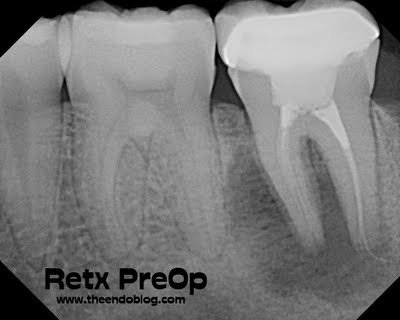

Huge periapical lesion noted. A thin, short (mesial) and long (distal) obturation.

DX: Prior RCT w/ Chronic Apical Abscess

2 yr recall shows fantastic healing. This tooth could easily have been condemned and extracted initially. Proper diagnosis, and ability to improve the cleaning, shaping and obturation allowed this tooth to be saved. Endodontists are specialists in saving teeth.